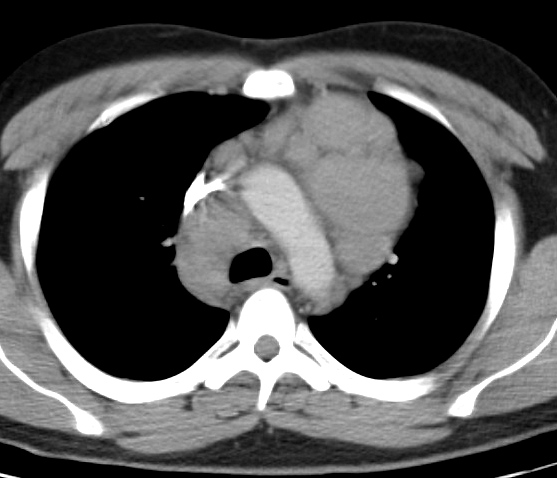

Gallery Mediastinum Lymphoma 5c

5c